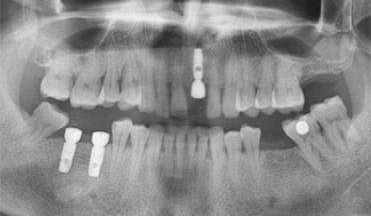

日常所说的假牙一般指烤瓷牙、活动假牙、种植牙等,其中种植牙较贵,但美观性、咀嚼功能的修复较好,后牙修复的话建议种植牙。

2、种植牙材料

材料不同、性能不一样,价格就会存在差异,品质越高的材料价格自然就越高。不同材质其机械性能、物理性能、化学性能、生物相容性、美观性等都有很大区别。当然也包括印模材料,模型材料,临时牙材料等。

3、牙齿种植难易程度

医生根据每个人的情况制定方案,治疗方法、难易程度不一样,价格也不一样。

4、患者口腔状况

口腔状况好的患者可直接进行手术,反之则需对口腔问题进行治疗后再种牙。》》》推荐阅读:种牙如何选择医院、医生、种植体?